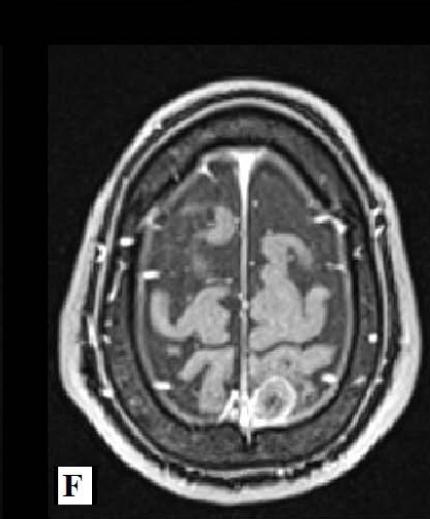

Laryssa Garcia de Almeida et al. Neurological Wilson Disease in a Young Brazilian Adult: A Case Report